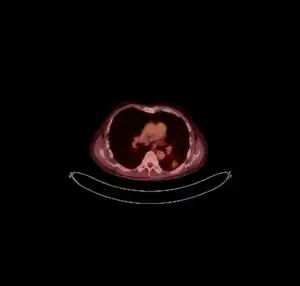

![]() ![]() text: From left to right: Cryptococcosis lung, cryptococcosis brain | |

FDG PET/CT - Multiple nodules (some cavitating) in the left lower lobe